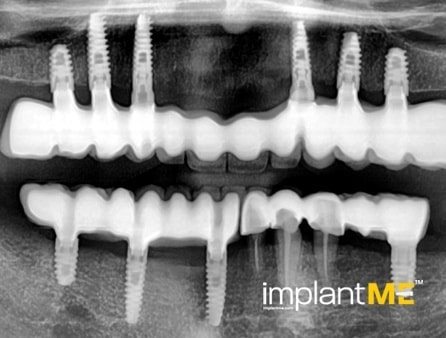

Атрактивните и особено здравите заби не се само одлучувачки дел од нашиот изглед, туку и на нашата личност. Во минатото, губењето на еден или повеќе заби имаше одлучувачка улога врз изгледот на луѓето. Поради модерната орална имплантологија, ова повеќе не е случај. Со релативно мали процедури за орална хирургија, индивидуалните или сите непостоечки заби можат да бидат заменети со импланти, естетски и функционално еднакви на природните заби. Преку вметнување импланти во форма на корен, можно е да се избегнат промени на соседните заби и да се зацврстат коронки што тешко може да се разликуваат од вистински заби во празнините на забите. Коронките или мостовите поддржани од импланти се прицврстени на колец зацврстен во коска, што им дава на пациентите џвакање со чувство скоро нималку различно од нивните заби. Во случај на потполна беззабост, имплантите може да претставуваат сигурна потпора за мобилна протеза, како и за големи фиксни мостови.

Забната протетика поддржана од имплант тесно се доближува до природните заби. Коронките водат со нивниот природен изглед, имплантите со нивната стабилност, а двете заедно со нивното позитивно влијание врз функционалното зачувување на целиот мастикаторен апарат.